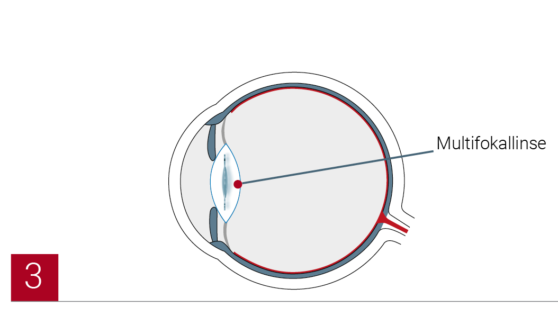

Die Operation erfolgt dabei durch einen ambulant durchgeführten chirurgischen Austausch der getrübten natürlichen Linse mit einer hochmodernen Kunstlinse (Intraokularlinse) – in der Regel mit einer Multifokallinse oder alternativ einer monofokalen Linse. Unsere Augenärzte in den EuroEyes-Kliniken haben bereits mehrere Tausend Graue-Star-Operationen erfolgreich vorgenommen. Die revolutionäre LenSx®-Lasertechnologie ermöglicht sogar eine klingenfreie Implantation.

Der Operateur setzt die neue Linse mit einem Injektor in das Auge ein. Die Linse entfaltet sich und wird vom Operateur in der leeren Linsenhülle richtig platziert. Sie kann ein Leben lang im Auge bleiben und kann entweder monofokal oder multifokal sein. Da eine Monofokallinse nur einen Brennpunkt hat, ist der Patient nach der Operation noch auf eine Brille angewiesen. Eine Multifokallinse hingegen hat mehrere Brennpunkte. Sie ermöglicht scharfes Sehen in unterschiedlichen Entfernungen und so ein brillenfreies Leben.

Die Behandlung des Grauen Star kann mit Mono- oder Multifokallinsen erfolgen. Multifokallinsen haben mehrere Brennpunkte. Der entscheidende Vorteil ist, dass der Patient nach der Behandlung wieder sowohl in der Nähe und mittleren Distanz also auch in der Ferne scharf sehen kann und nicht mehr auf Lese- oder Gleitsichtbrille angewiesen ist. Monofokallinsen weisen im Gegensatz dazu nur einen Brennpunkt auf. Sie können daher nur das Sehen entweder in der Nahe oder in der Ferne verbessern. Die völlige Unabhängigkeit von der Brille kann mit Monofokallinsen nicht gewährleistet werden.

Der Operateur setzt die neue Linse mit einem Injektor in das Auge ein. Die Linse entfaltet sich und wird vom Operateur in der leeren Linsenhülle richtig platziert. Sie kann ein Leben lang im Auge bleiben und kann entweder monofokal oder multifokal sein. Da eine Monofokallinse nur einen Brennpunkt hat, ist der Patient nach der Operation noch auf eine Brille angewiesen. Eine Multifokallinse hingegen hat mehrere Brennpunkte. Sie ermöglicht scharfes Sehen in unterschiedlichen Entfernungen und so ein brillenfreies Leben.

Die Behandlung des Grauen Star kann mit Mono- oder Multifokallinsen erfolgen. Multifokallinsen haben mehrere Brennpunkte. Der entscheidende Vorteil ist, dass der Patient nach der Behandlung wieder sowohl in der Nähe und mittleren Distanz also auch in der Ferne scharf sehen kann und nicht mehr auf Lese- oder Gleitsichtbrille angewiesen ist. Monofokallinsen weisen im Gegensatz dazu nur einen Brennpunkt auf. Sie können daher nur das Sehen entweder in der Nahe oder in der Ferne verbessern. Die völlige Unabhängigkeit von der Brille kann mit Monofokallinsen nicht gewährleistet werden.